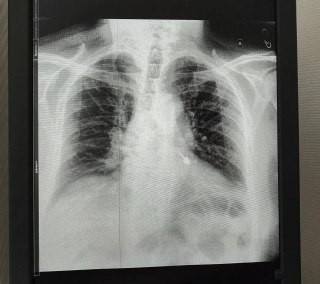

🦷 Стоматологический бур провалился в бронхи мужчины во время лечения зубов в Подмосковье.

Он сразу почувствовал боль в груди и обратился в больницу. Врачи с помощью эндоскопа извлекли инструмент, сейчас с пациентом всё в порядке.